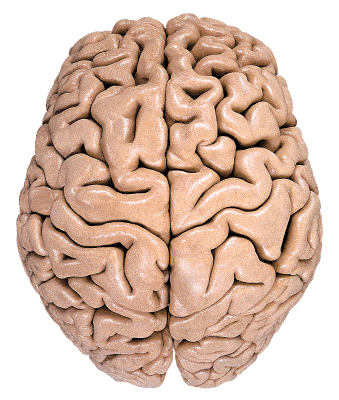

El cerebro presenta una superficie lisa durante los primeros meses de desarrollo intrauterino, hasta aproximadamente el tercer mes. Sin embargo, a medida que avanza el desarrollo embrionario, la corteza cerebral, también conocida como manto o pallium, experimenta un crecimiento considerable. Este crecimiento provoca que la superficie del cerebro se pliegue, generando surcos que delimitan áreas de mayor complejidad llamadas giros o circunvoluciones.

El desarrollo de los surcos y giros en la superficie del cerebro tiene importantes implicaciones funcionales. A medida que el cerebro se pliega y forma surcos y giros, se incrementa significativamente el área de la corteza cerebral disponible para el procesamiento de información. Esta mayor superficie cortical permite una mayor cantidad de neuronas y conexiones sinápticas, lo que contribuye a la capacidad cognitiva y las funciones cerebrales superiores.

En la superficie de los hemisferios cerebrales, se pueden observar surcos más profundos que otros, conocidos como surcos interlobares. Estos surcos interlobares ayudan a delimitar los lóbulos cerebrales, que son regiones funcionales específicas en la superficie del cerebro. Los lóbulos cerebrales, como el lóbulo frontal, parietal, temporal y occipital, tienen funciones especializadas y se asocian con diferentes aspectos del comportamiento, la percepción y el procesamiento de la información.

Dentro de los lóbulos cerebrales, se pueden observar surcos menos profundos que delimitan los giros. Estos giros son salientes más o menos flexuosas y representan áreas más específicas de la corteza cerebral. Cada giro cerebral tiene una función particular y puede estar involucrado en procesos cognitivos específicos, como la memoria, el lenguaje, la percepción sensorial o el control motor.

Es importante destacar que los giros de un mismo lóbulo pueden estar reunidos por pliegues, lo que proporciona una organización y estructura más precisa en la superficie del cerebro. Estos pliegues ayudan a separar y definir las áreas funcionales dentro de un lóbulo determinado.

En conjunto, los surcos y giros del cerebro humano permiten una mayor eficiencia en el procesamiento de la información al proporcionar una mayor superficie cortical y una organización funcional más detallada. Estas características son distintivas del cerebro humano y se asocian con nuestras capacidades cognitivas superiores.